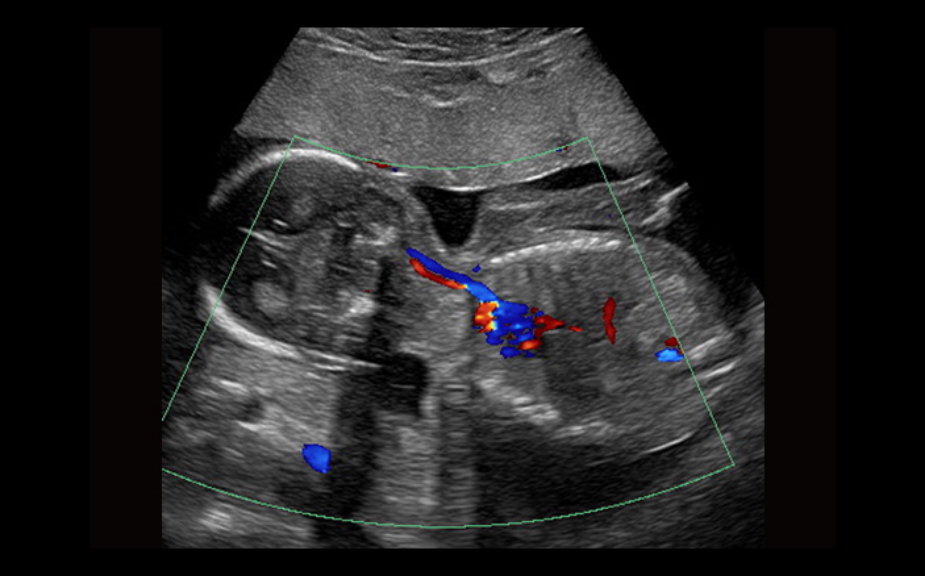

Equipado con software patentado con base en tecnolog├Ła ZONE?Sonography? (ZST),?el Z.One PRO proporciona toma de im├Īgenes Doppler y Modo-B detalladas ├│ptimamente para pacientes, sin importar la complexi├│n del cuerpo, ayudando a asegurar un diagn├│stico confiable.

A trav├®s de una amplia gama de aplicaciones, el Z.One PRO es la soluci├│n de ultrasonido para sus exigentes desaf├Łos cl├Łnicos.

- Insuperable calidad de imagen en todas las aplicaciones

- Compatible con CEUS en transductores abdominales